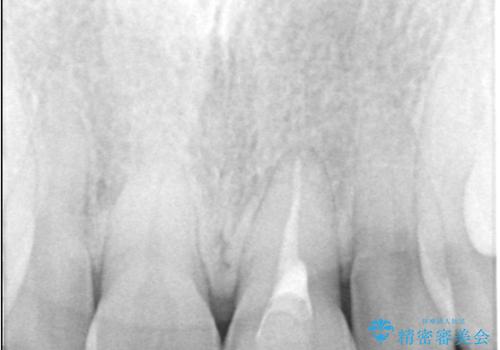

過去に神経の治療をした歯に変色がみられました。ラバーダム防湿の重要性を説明し、予防的に再根管治療から行い、被せ物をすることとなりました。